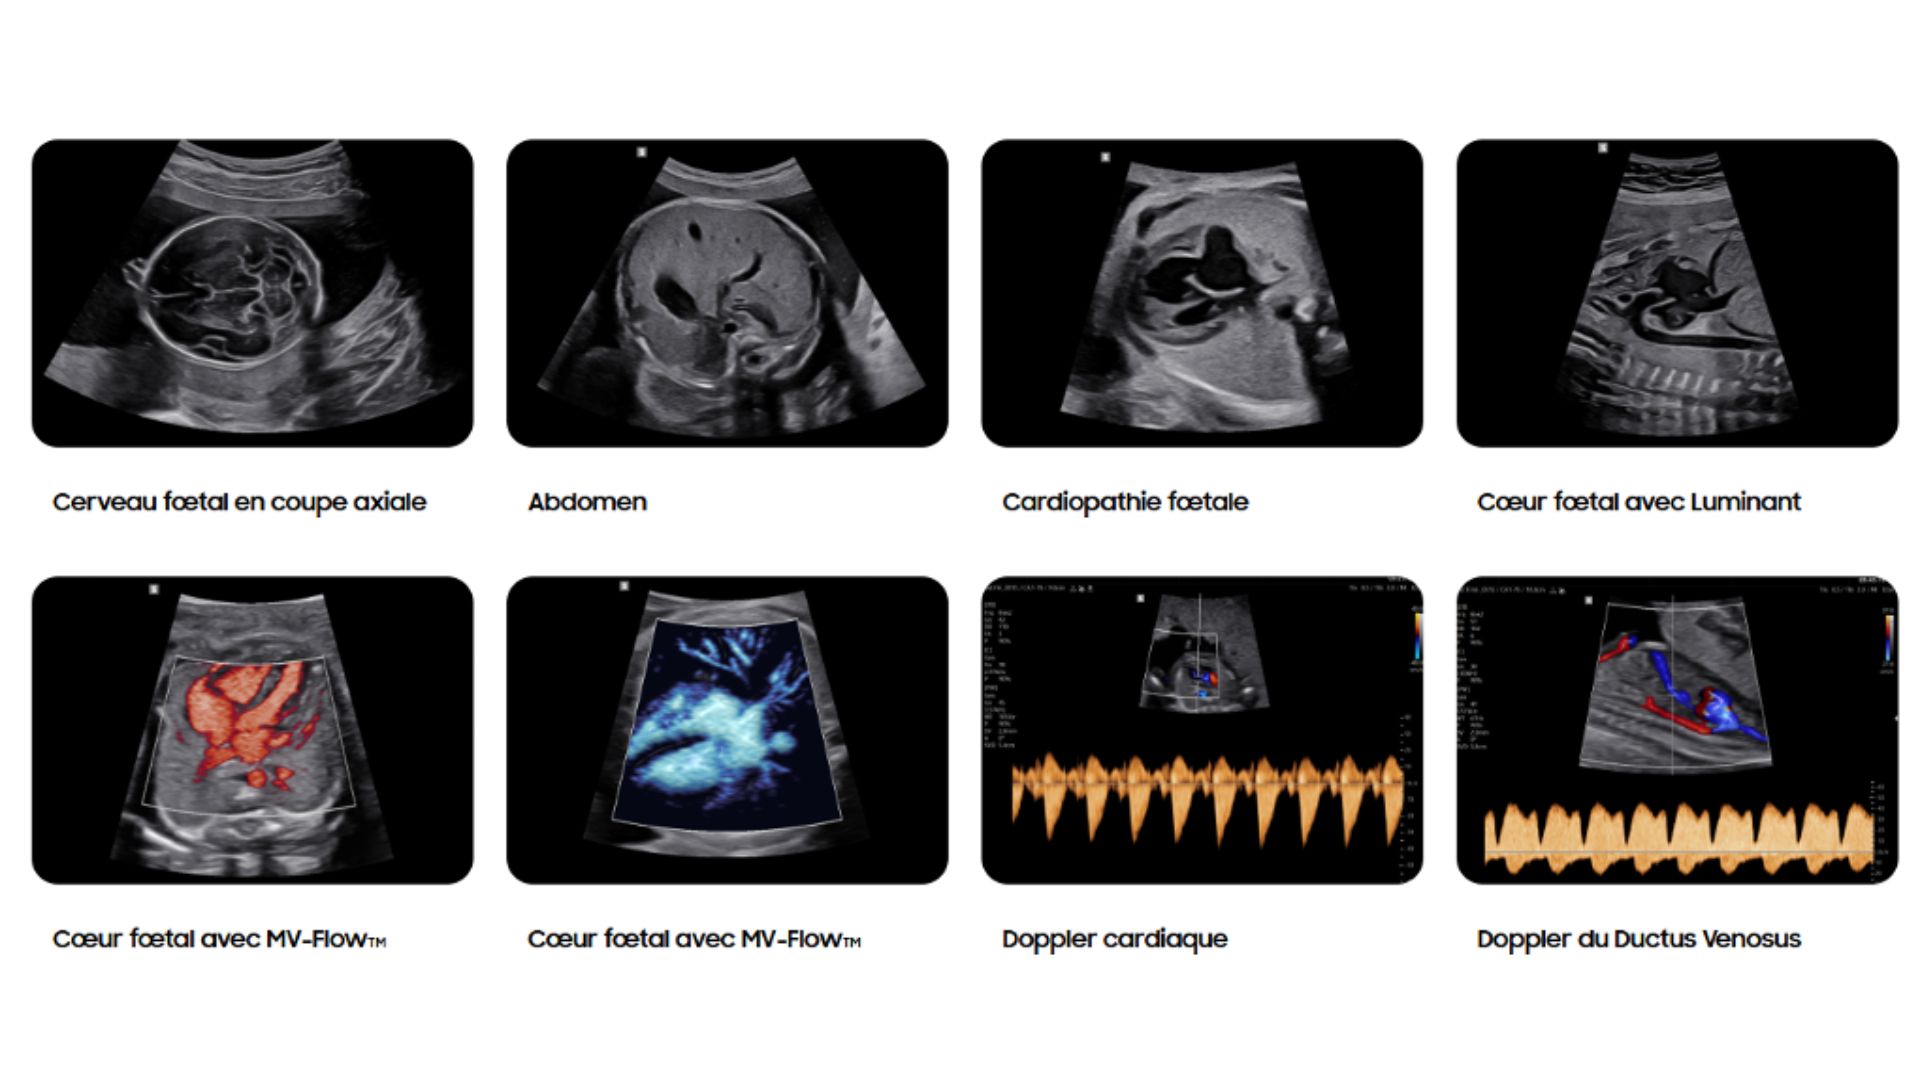

Luminant™ est un algorithme de différenciation structurelle qui transforme les contours d’une image 2D et améliore l’analyse des structures, comme pour le cœur ou le cerveau fœtal.

L’outil HeartAssist™, basé sur la reconnaissance d’images, permet d’identifier les structures de l’image échographique afin de réaliser automatiquement les mesures nécessaires à l’analyse du cœur fœtal. Il génère ensuite des résultats précis, ainsi que le tracé des courbes de normalité.